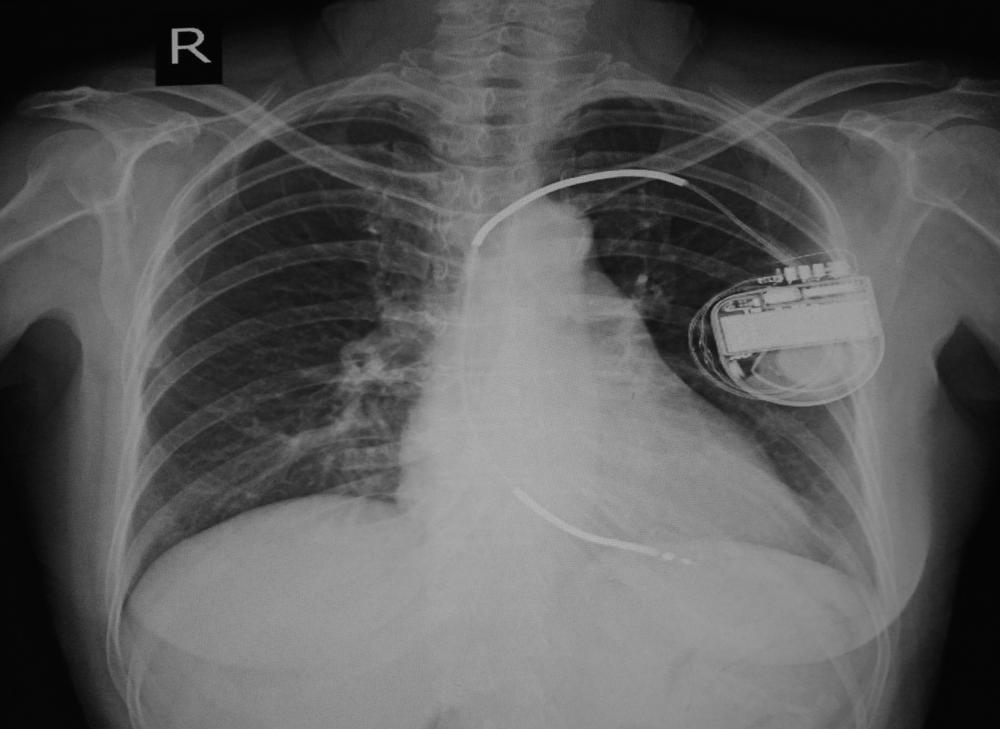

Menurut Robert Hauser, MD, seorang ahli jantung dari Minneapolis Heart Institute, Amerika Serikat, kedua kondisi tersebut dapat meningkatkan risiko kematian jantung mendadak dan gagal jantung. Oleh karena itulah dibutuhkan bantuan alat pacu jantung implan untuk membantu meningkatkan aliran darah ke jantung dan seluruh tubuh.

Sebelum memasang defibrilator, pastikan Anda sudah mengantongi izin dari dokter spesialis jantung Anda terlebih dahulu. Dokter akan melihat riwayat kesehatan Anda dan mengukur seberapa besar Anda membutuhkan pacu jantung.

Setelah operasi tanam alat pacu ini berhasil, selalu ikuti semua anjuran dokter spesialis jantung mengenai hal-hal yang boleh dan tidak boleh Anda lakukan. Ini bertujuan untuk mencegah efek samping dan risiko yang mungkin terjadi pada tubuh Anda setelah memasang defibrilator.